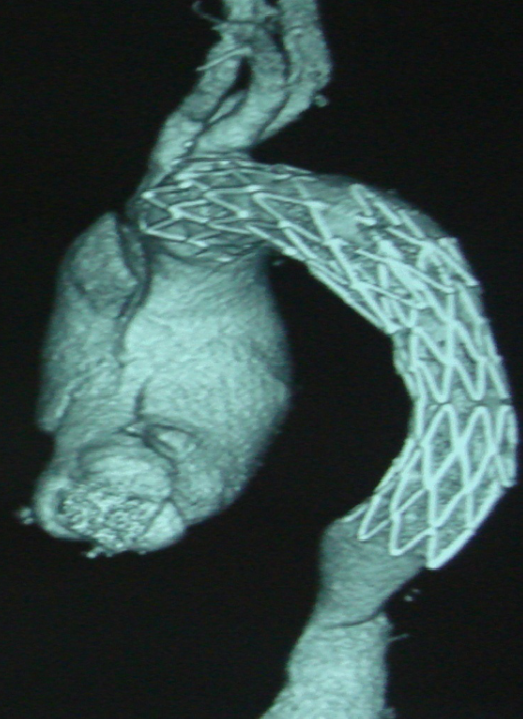

男,49岁,急性AD。2019年1月TEVAR,3月RTAD,行全弓置换+支架象鼻。2022 年1月25日术后复查,结果良好。